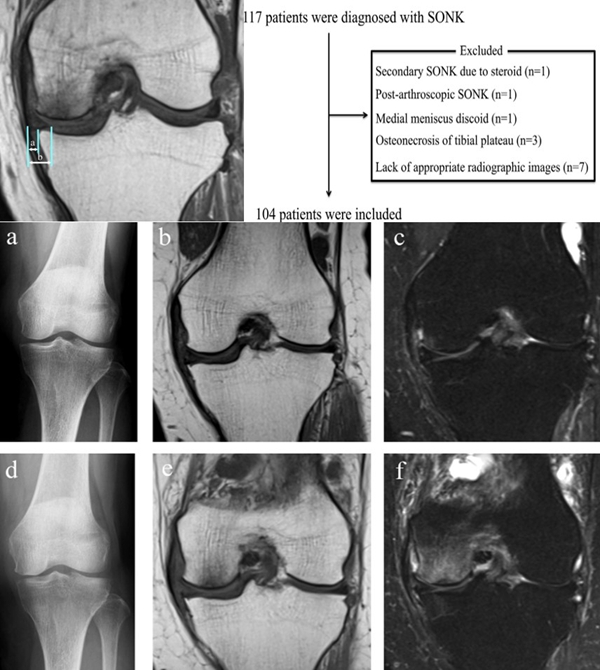

膝关节自发性骨坏死(spontaneous osteonecrosis of the knee,SONK)是指发生于股骨内侧髁负重面深层、原因不明的局部骨坏死,也可发生于股骨外侧髁或胫骨平台,在1968年由Ahlback等首先描述。

X线+MRI:通过测量正位X线片和MRI判断坏死区域的大小。

目前SONK诊断最常用的分期方法是1979年Koshino提出的分期法。Koshino分期基于临床和影像学的结果,将SONK分为四个阶段:

Ⅰ期:患者有膝关节症状,但影像学正常;

Ⅱ期:X线显示负重区变平,软骨下信号升高,周围有骨硬化;

Ⅲ期:受影响区域扩大和软骨下塌陷;

Ⅳ期:病变周围骨硬化和髁突周围骨赘形成的退行性阶段。

1979年Koshino分期